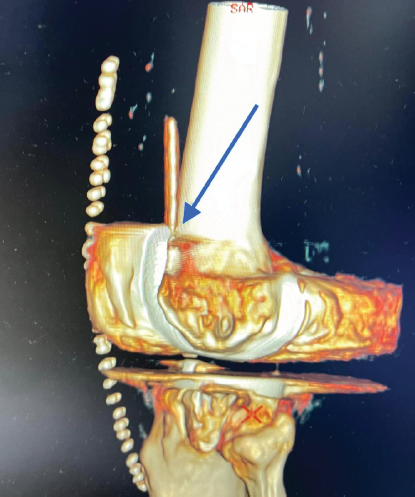

A 69-year-old male with Grade IV osteoarthritis of the right knee underwent primary total knee arthroplasty using an identical surgical technique and drain placement as described above. At 24 h postoperatively, drain removal was attempted with the knee in extension, with gentle traction. The drain broke during removal, leaving the proximal segment retained within the joint. 3D CT scan showed that the retained segment was impinged between the articular surface of the patella and the femoral implant (Fig. 3).

Figure 3: 3D computed tomography scan showing the point of impingement (indicated by blue arrow).

In Case 2, the drain broke while being removed with the knee in extension. This may have been due to weakening from impingement between the articular surface of the patella and the femoral component, which was confirmed on the 3D CT scan.